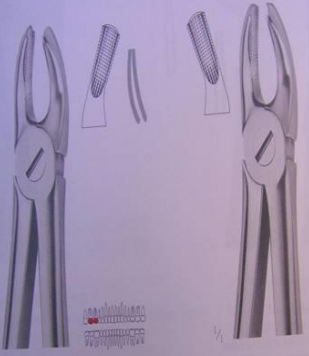

Instrumentation : le Davier

Description

Un davier est formé de trois parties :

- Mors : Partie travaillante, permettant de saisir la dent grâce à leur forme adaptée à la morphologie dentaire.

- Branches : Généralement symétriques, légèrement courbées.

- Charnière : Point d’union des deux bras de l’instrument.

Variétés

Au maxillaire supérieur

Les mors sont dans le prolongement du manche.

- Daviers pour incisives et canines :

- Forme générale rectiligne.

- Daviers pour prémolaires :

- Mors identiques.

- Forme générale en S italique.

- Branches incurvées.

- Daviers pour 1re et 2e molaires :

- Forme générale en S étiré.

- Mors asymétriques : en vestibulaire, le mors possède un éperon médian qui s’insère entre les deux racines vestibulaires (mésiale et distale).

- Existe en version droite et gauche.

- Daviers pour dents de sagesse :

- Forme en baïonnette.

- Absence d’ergots.

- Utilisation bilatérale (dents de sagesse droite et gauche).

- Daviers pour racines :

- Mors fins et longs.

Au niveau mandibulaire

Les mors forment un angle droit avec les manches.

- Daviers pour incisives et canines.

- Daviers pour prémolaires.

- Daviers pour 1re et 2e molaires.

- Daviers pour dents de sagesse.

- Daviers pour racines.